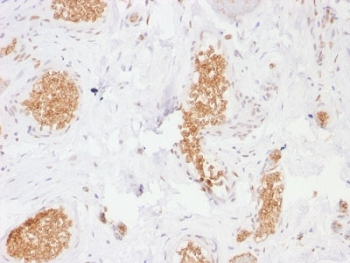

IHC staining of FFPE human esophagus tissue with SLC2A1 antibody (clone GLUT1/7308). Inset: PBS used in place of primary Ab (secondary Ab negative control). HIER: boil tissue sections in pH9 10 mM Tris with 1 mM EDTA for 20 min and allow to cool before testing.

IHC staining of FFPE human ovarian carcinoma tissue with SLC2A1 antibody (clone GLUT1/7308). Inset: PBS used in place of primary Ab (secondary Ab negative control). HIER: boil tissue sections in pH9 10 mM Tris with 1 mM EDTA for 20 min and allow to cool before testing.